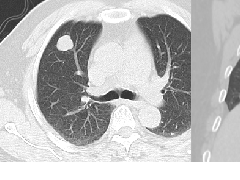

CT urogram (2017): Noncontrast images demonstrate multiple bilateral nonobstructing renal calculi, the largest measuring 6 mm in the right kidney. Some of the calcifications could represent nephrocalcinosis — for example, those in the upper pole of the right kidney. The kidneys show symmetric enhancement without suspicious renal mass. Multiple bilateral exophytic simple renal cysts are noted, the largest in the midpole of the right kidney measuring 3.6 x 4.3 cm. There are additional subcentimeter low-attenuation lesions that are too small to characterize. There is a “paintbrush sign” appearance to the renal medullae in keeping with a history of medullary sponge kidney. There is mild bladder wall thickening and trabeculation that may be related to chronic outlet obstruction. Further evaluation is deferred to cystoscopy.

CTU:CT平扫可见双肾多发非梗阻性肾结石,右肾最大者直径约6mm,其中一些钙化可能代表肾结石,例如,右肾上极的那些。肾脏对称性强化,未见可疑肾肿物。双肾可见多发单纯性肾囊肿,大者位于右肾中部,大小约3.6 x 4.3 cm;另可见不足1cm的低密度灶,其太小而不能显示。肾髓质表现为“毛刷征”,符合髓质海绵肾。膀胱壁轻度增厚并小梁形成,与慢性流出道梗阻有关。进一步评估需膀胱镜检查。